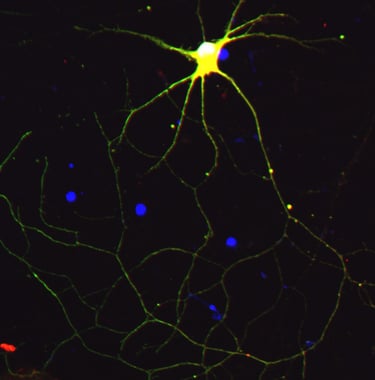

iPSC-derived Neurons